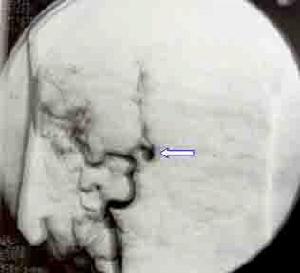

自發性蛛網膜下腔出血CT圖動脈瘤為最常見的出血原因大宗文獻統計表明動脈瘤出血占蛛網膜下腔出血病人的52%。此外,尚有一部分查不清死因者,其所占的比例受診斷條件影響,過去曾高達46.3%。隨著檢查手段的進步,對蛛網膜下腔出血的病因檢出率增加,不明原因的比例下降為9%~20%。血液病、顱內感染、藥物中毒等造成蛛網膜下腔出血者也偶見。

自發性蛛網膜下腔出血發病機制1.誘發因素 約有1/3的動脈瘤破裂發生於劇烈運動中如:舉重、情緒激動、咳嗽、屏便、房事等。如前所述,吸菸、飲酒也是蛛網膜下腔出血的危險因素。